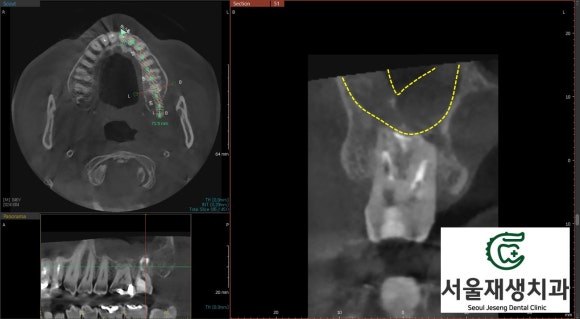

먼저 환자분의 통증 내력을 경청하고, 정확한 진단을 위해 육안검사 및 영상검사를 진행했습니다.

신경치료를 받은 치아에서 염증이 재발한 케이스.

상악동까지 감염이 전파되었습니다.

윗 어금니에 발생한 염증은 상악동(부비동의 하나, 광대뼈 하방에 존재하는 계란만한 크기의 빈 공간. 코와 연결되어 있음)으로 파급될 가능성이 있기에 CT를 촬영합니다.

상악동은 치아의 뿌리와 매우 가까운 위치에 있어 치아 염증이 상악동염으로 이어지는 경우가 종종 있기 때문입니다.

신경치료와 관련하여 촬영하는 CT는 건강보험이 적용되어 대략 2만원 초반의 비용이 발생합니다.

검사 결과, 상악동 내부에 염증이 가득 차 있는 것을 확인했습니다.